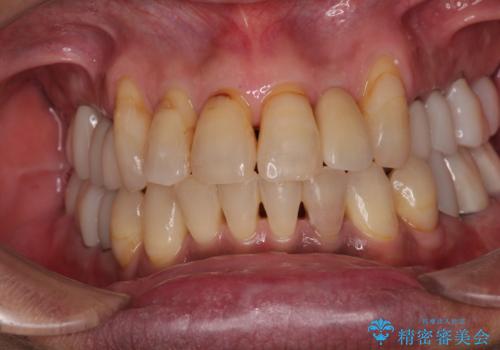

前歯のインプラント治療は、従来の抜歯から数ヶ月待機する手法では、骨造成や歯肉移植など付随の処置が多く必要となり、費用、期間、身体的負担のいずれもが多大となります。

抜歯時にインプラントを埋入することでそれらの負担を大きく軽減させることが可能です。